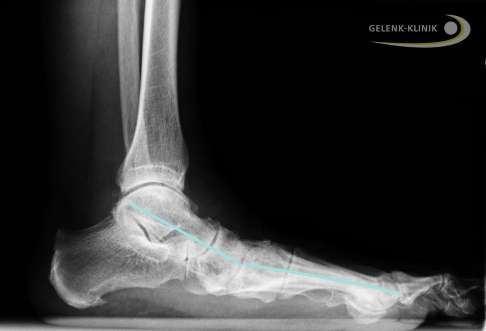

Röntgenbild von Fuß und Sprunggelenk (Längsschnitt). Die Linie zeigt das sichtbar abgesenkte Fußlängsgewölbe. Der dadurch nach innen geknickte Fuß führt zu einer Überlastung am Innenknöchel. Eine Sprunggelenksarthrose ist die mögliche Folge. © Dr. Thomas Schneider

Nicht nur Unfälle, auch Fußfehlstellungen gefährden die Gesundheit des oberen Sprunggelenks. Der Fuß ist ein entscheidend wichtiges Stellungsorgan, das die Ausrichtung der Gelenkpartner zueinander im Sprunggelenk bestimmt.

Bei einem Senkfuß kippt der Sprungbeinknochen oft nach vorne und unten ab. Dadurch entsteht aufgrund der kegelförmigen anatomischen Form des Sprungbeins eine Instabilität im oberen Sprunggelenk: Es kommt zu Sprunggelenkschmerzen am Innenknöchel.